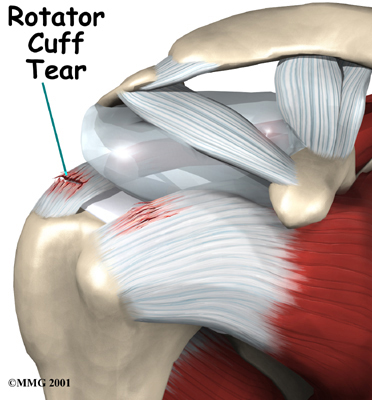

Rotator Cuff Tendonitis

Rotator cuff problems of the shoulder range from mild damage to:

Complete Tears

They can cause pain even when resting.

Related Document: FYZICAL Naples (Pelican Bay)'s Guide to Rotator Cuff Disease

Some researchers think that a decreased blood supply to the tendons can cause the tendon damage in tendonosis. The decreased blood supply does not allow the tendon to get enough oxygen from the blood. This leads to a condition where the tendon degenerates. The collagen material that makes up the tendon actually becomes weaker and loses its nylon rope appearance. This type of degeneration has been noted in the rotator cuff around the shoulder, in the Achilles tendon in the heel and in the tendons of the elbow.